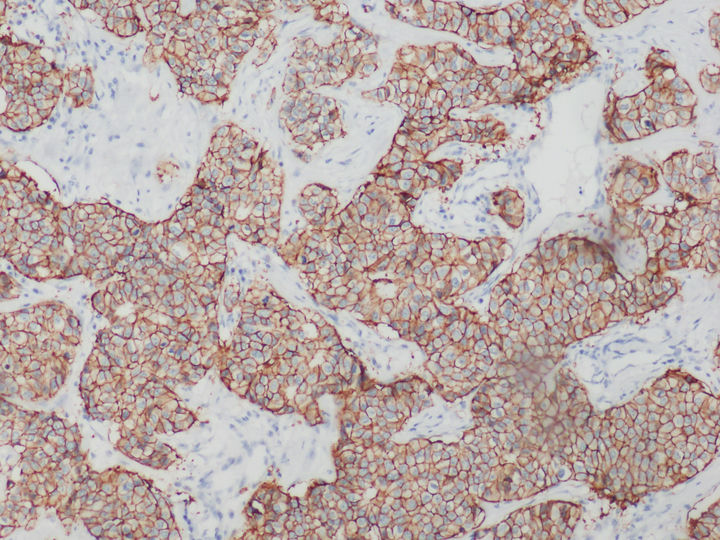

熒光顯微鏡下的乳腺癌HER2檢測

HER是一類與細胞增殖息息相關(guān)的蛋白質(zhì),全稱是human epidermal growth factor receptor,中文叫作人表皮生長因子受體。HER蛋白質(zhì)家族共有四兄弟,其中HER2負責將細胞膜外的生命信息傳導至細胞內(nèi),是乳腺癌診斷指標之一,檢測HER2一般用正置熒光顯微鏡,使用免疫組化或熒光原位雜交FISH技術(shù)。

在乳腺癌,胃癌等腫瘤篩查領(lǐng)域中,HER2的表達水平是腫瘤檢測的常用指標。目前,HER2基因檢測常見方式以免疫組化IHC技術(shù)和FISH技術(shù)為主。

免疫組化HER2檢測可以用普通顯微鏡明場觀察實現(xiàn),設(shè)備要求較低,但靈敏度和特異性相對弱。